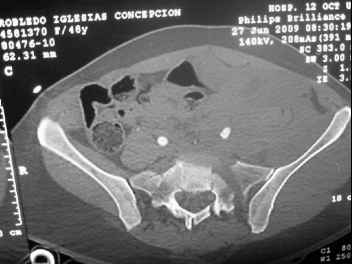

This complex and displaced sacral injury is likely an H pattern...2 hemipelvic components, an upper sacral component which remains attached to the lumbar spine, and a caudal sacral component...there are typically anterior ring injuries as well...in this patient's example, the left sided acetabulum also has been exploded.

Most H pattern sacral fractures have the transverse fracture limb of the "H" at the upper-second sacral segment junction or disc region...some fracture thru the second segment, and some or at other sites...but most yield thru the upper-second sacral segments junction...with variable traumatic associated neurological findings.

The transverse fracture limb liberates the upper sacral segment and its attached lumbar-thoracic-cervical spine to displace...usually anteriorly and in kyphosis.

The kyphosis and anterior translation of the upper sacral segment distorts the safe area for iliosacral screw usage...the imaging allows the surgeon to preoperatively plan if iliosacral screw fixation is a safe possibility.